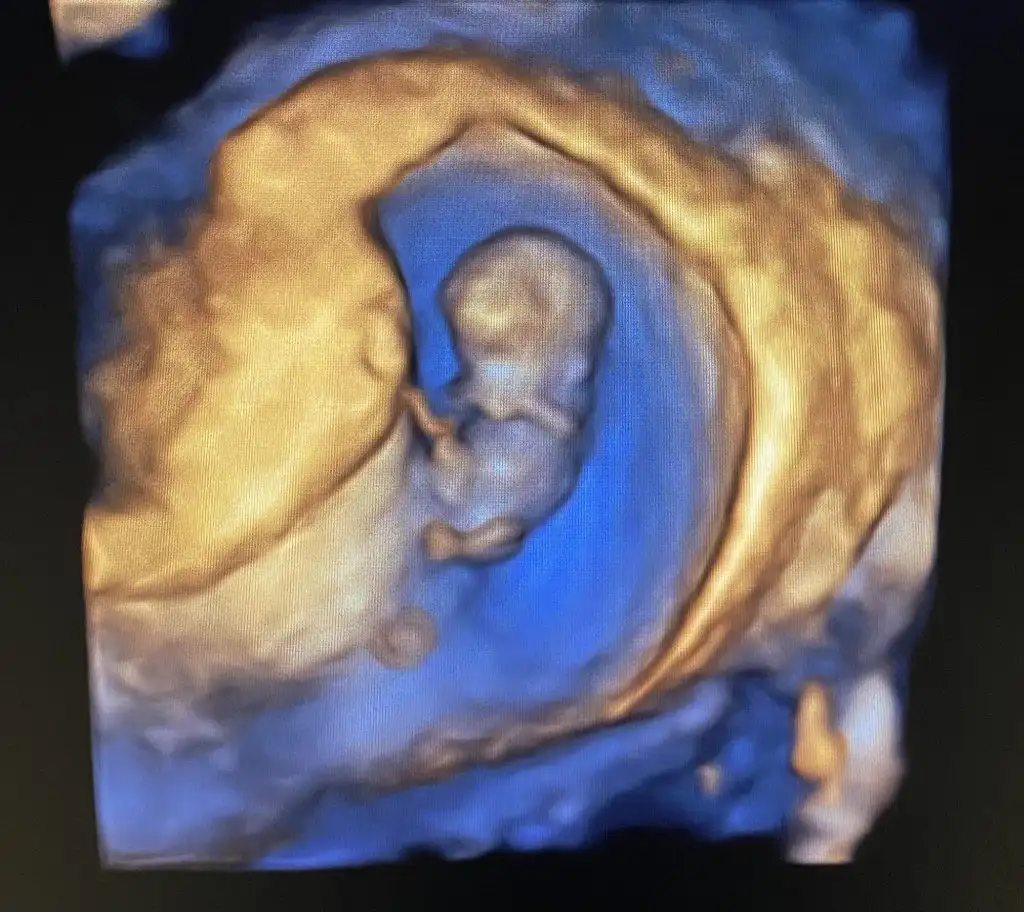

İkili testte 3. De ense ölçümü zor aldılar hareketli pozisyon vermedi 13. Haftada bir doktora gittim göstermedi sabahsi başka bir doktor bacak arasını gösterdi erkek büyük ihtimalle dedi dün 13 haftadaki ilk doktora gittim bacak arasından kordon geciyor cinsiyet görünmüyor cinsiyeti örtmüş tahminde bulunamam dedi bende bu defa acaba diğer doktorun gördüğü kordon muydu kordonu pipi mi zannetti diyorum çünkü bir tek o tahminde bulundu

Attığınız görüntülerde ben asla pipiye benzer bişey göremedim, doktorun baktığı açı tabikide daha iyi onlar canlı canlı bakıyor. Bi 2 hafta daha bekleyin bakalım, gitmeden önce kontrole de biraz yürüyüş yapın su için bol bol görünür belki ❤️

bize de erkek dedi 16, haftadayız sizce yanılma payı olabilir mi ikinci fotoğraftaki organı mı acaba